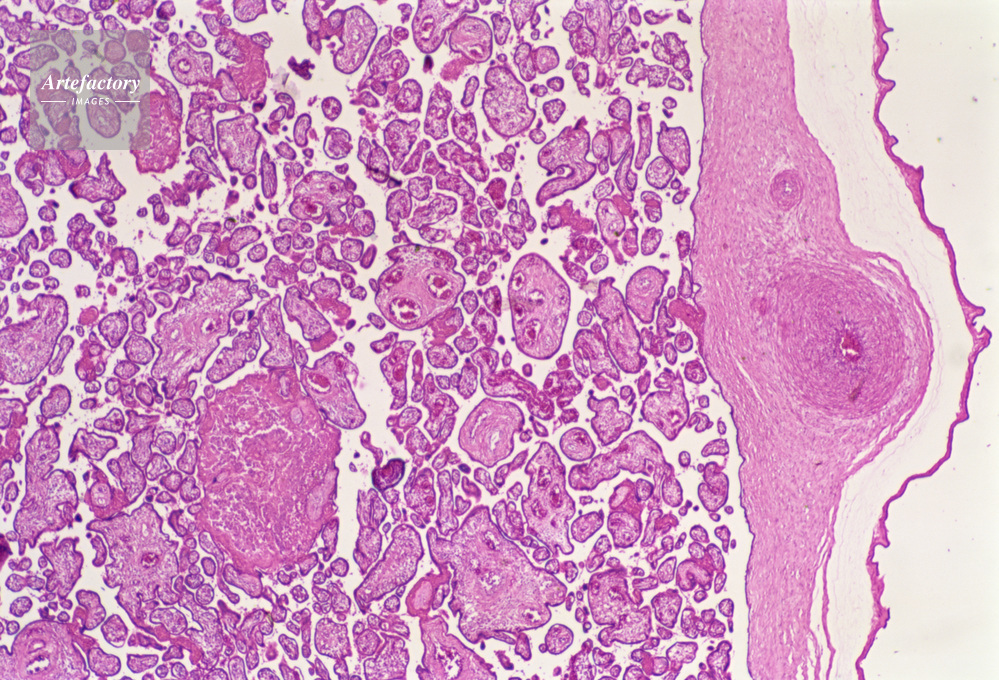

| キャプション | 胎盤,人間,20倍 | 制限事項 | ||

| ソース | ピクセル数 | 5552px × 3778px | ||